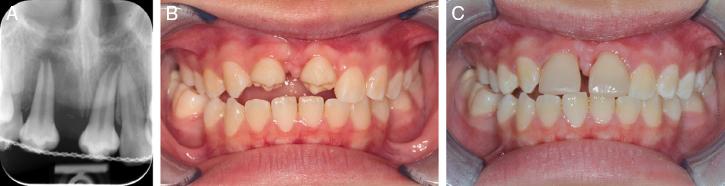

Figure 2.